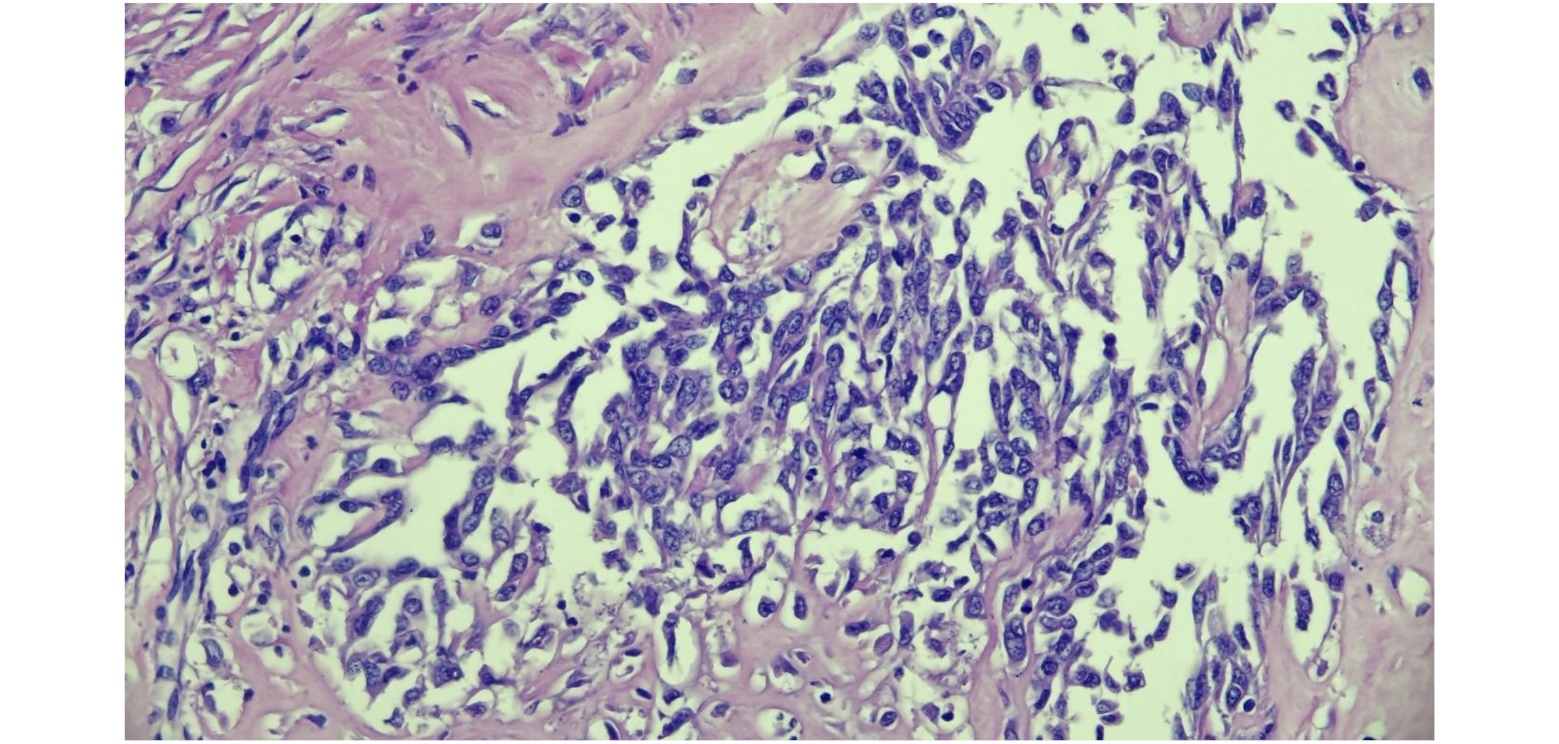

Besides not possible to visualize in macroscopy, the lungs also presented the same microscopic examination of all the regions (Fig.2): a marked cellular infiltrate been irregular, multifocal and non-encapsulated. The cells exhibited an irregular tubule-papillary arrangement, sometimes isolated amidst intense fibrocollagenous stroma. They were polyhedral to elongated, intermediate in size, with moderate to scarce, eosinophilic, vacuolated to homogeneous cytoplasm. They had a rounded, centralized nucleus with coarsely dotted chromatin and 0 to 3 intermediate and conspicuous nucleoli. Marked anisokaryosis, anisocytosis and moderate cellular pleomorphism were observed. The neoplasm exhibited low mitotic activity, with 7 mitotic figures observed in 2.37mm², with moderate binucleated and multinucleated cells (Fig.3). Additionally, presence of an intense multifocal to coalescent necrosis and intense, multifocal bone and cartilaginous metaplasias (Fig. 4).

Figure. 3. Polyhedral to elongated cells with intermediate size, moderate to scarce, eosinophilic, vacuolated cytoplasm. A rounded, centralized nucleus with coarsely dotted chromatin and 0 to 3 intermediate and conspicuous nucleoli. Marked anisokaryosis, anisocytosis and moderate cellular pleomorphism, with moderate binucleated and multinucleated cells.